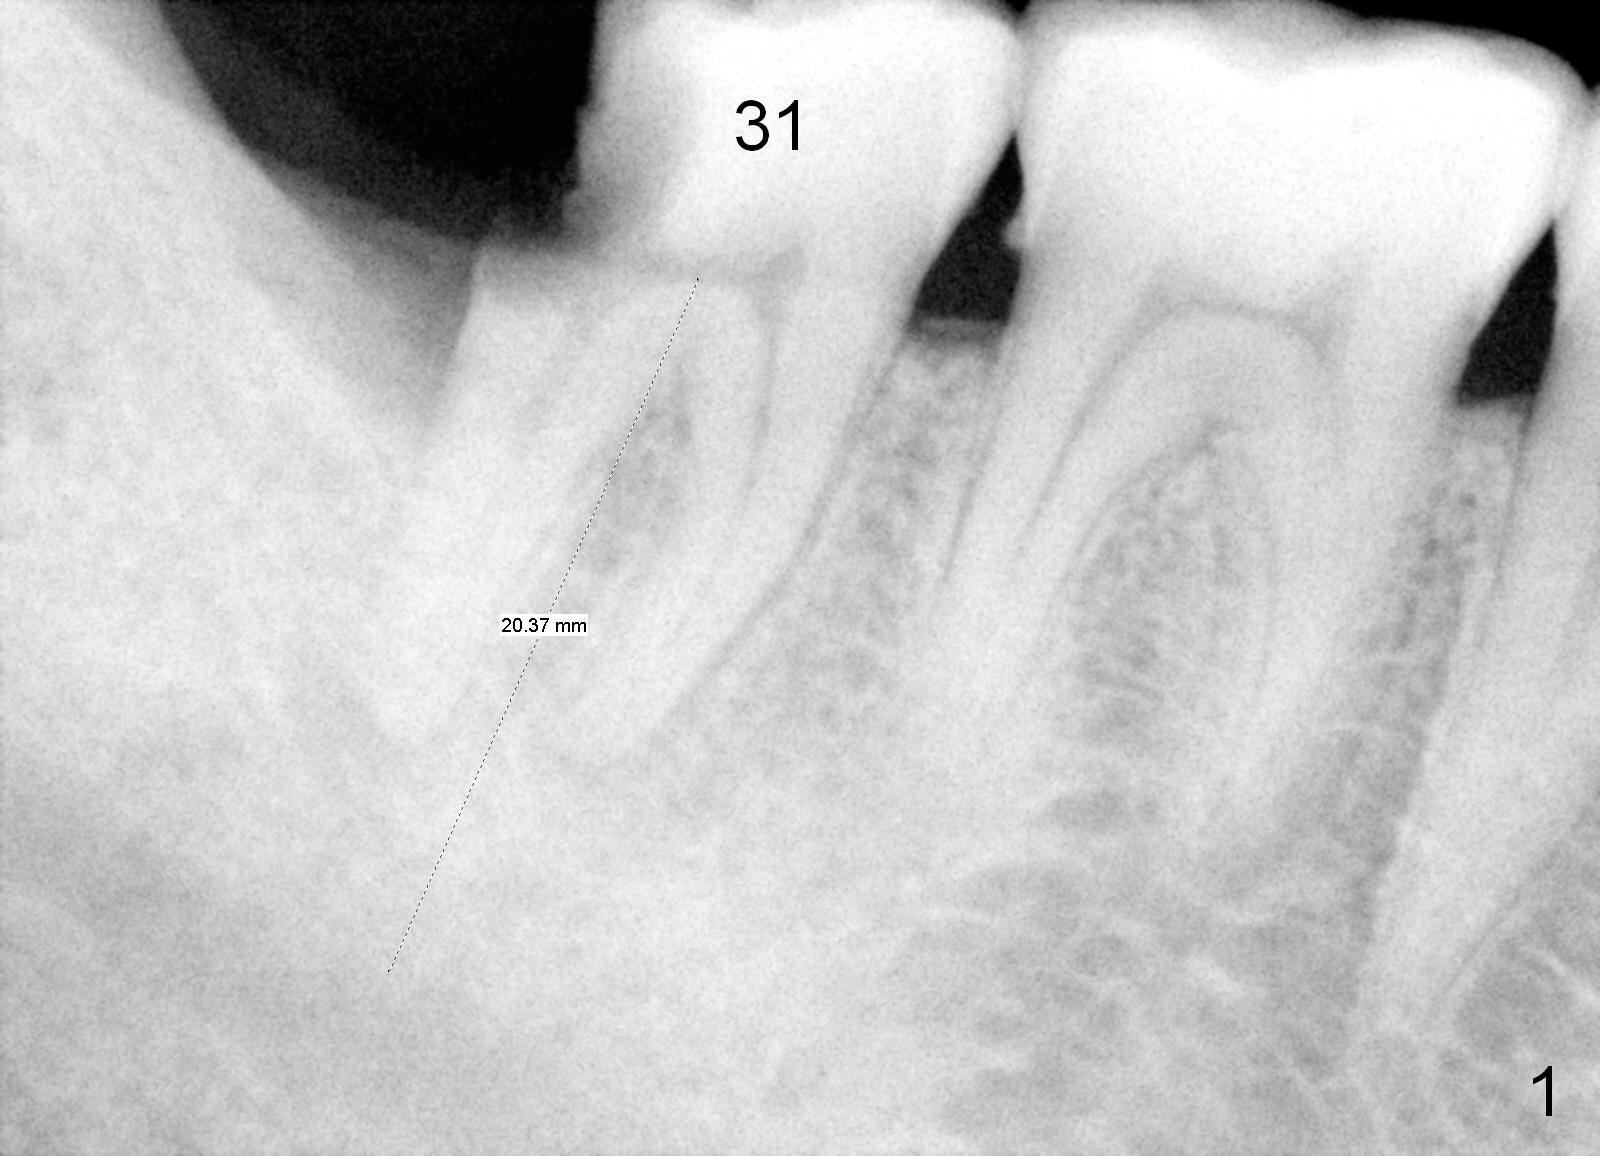

There appears to be bone loss coronally 15 months postop (Fig.8). There is no bone loss 1 year post cementation (2 years 3 months postop, Fig.9). If the implant were longer, it might perforate the lingual (L) plate (Fig.10 (1.5 years post cementation)).